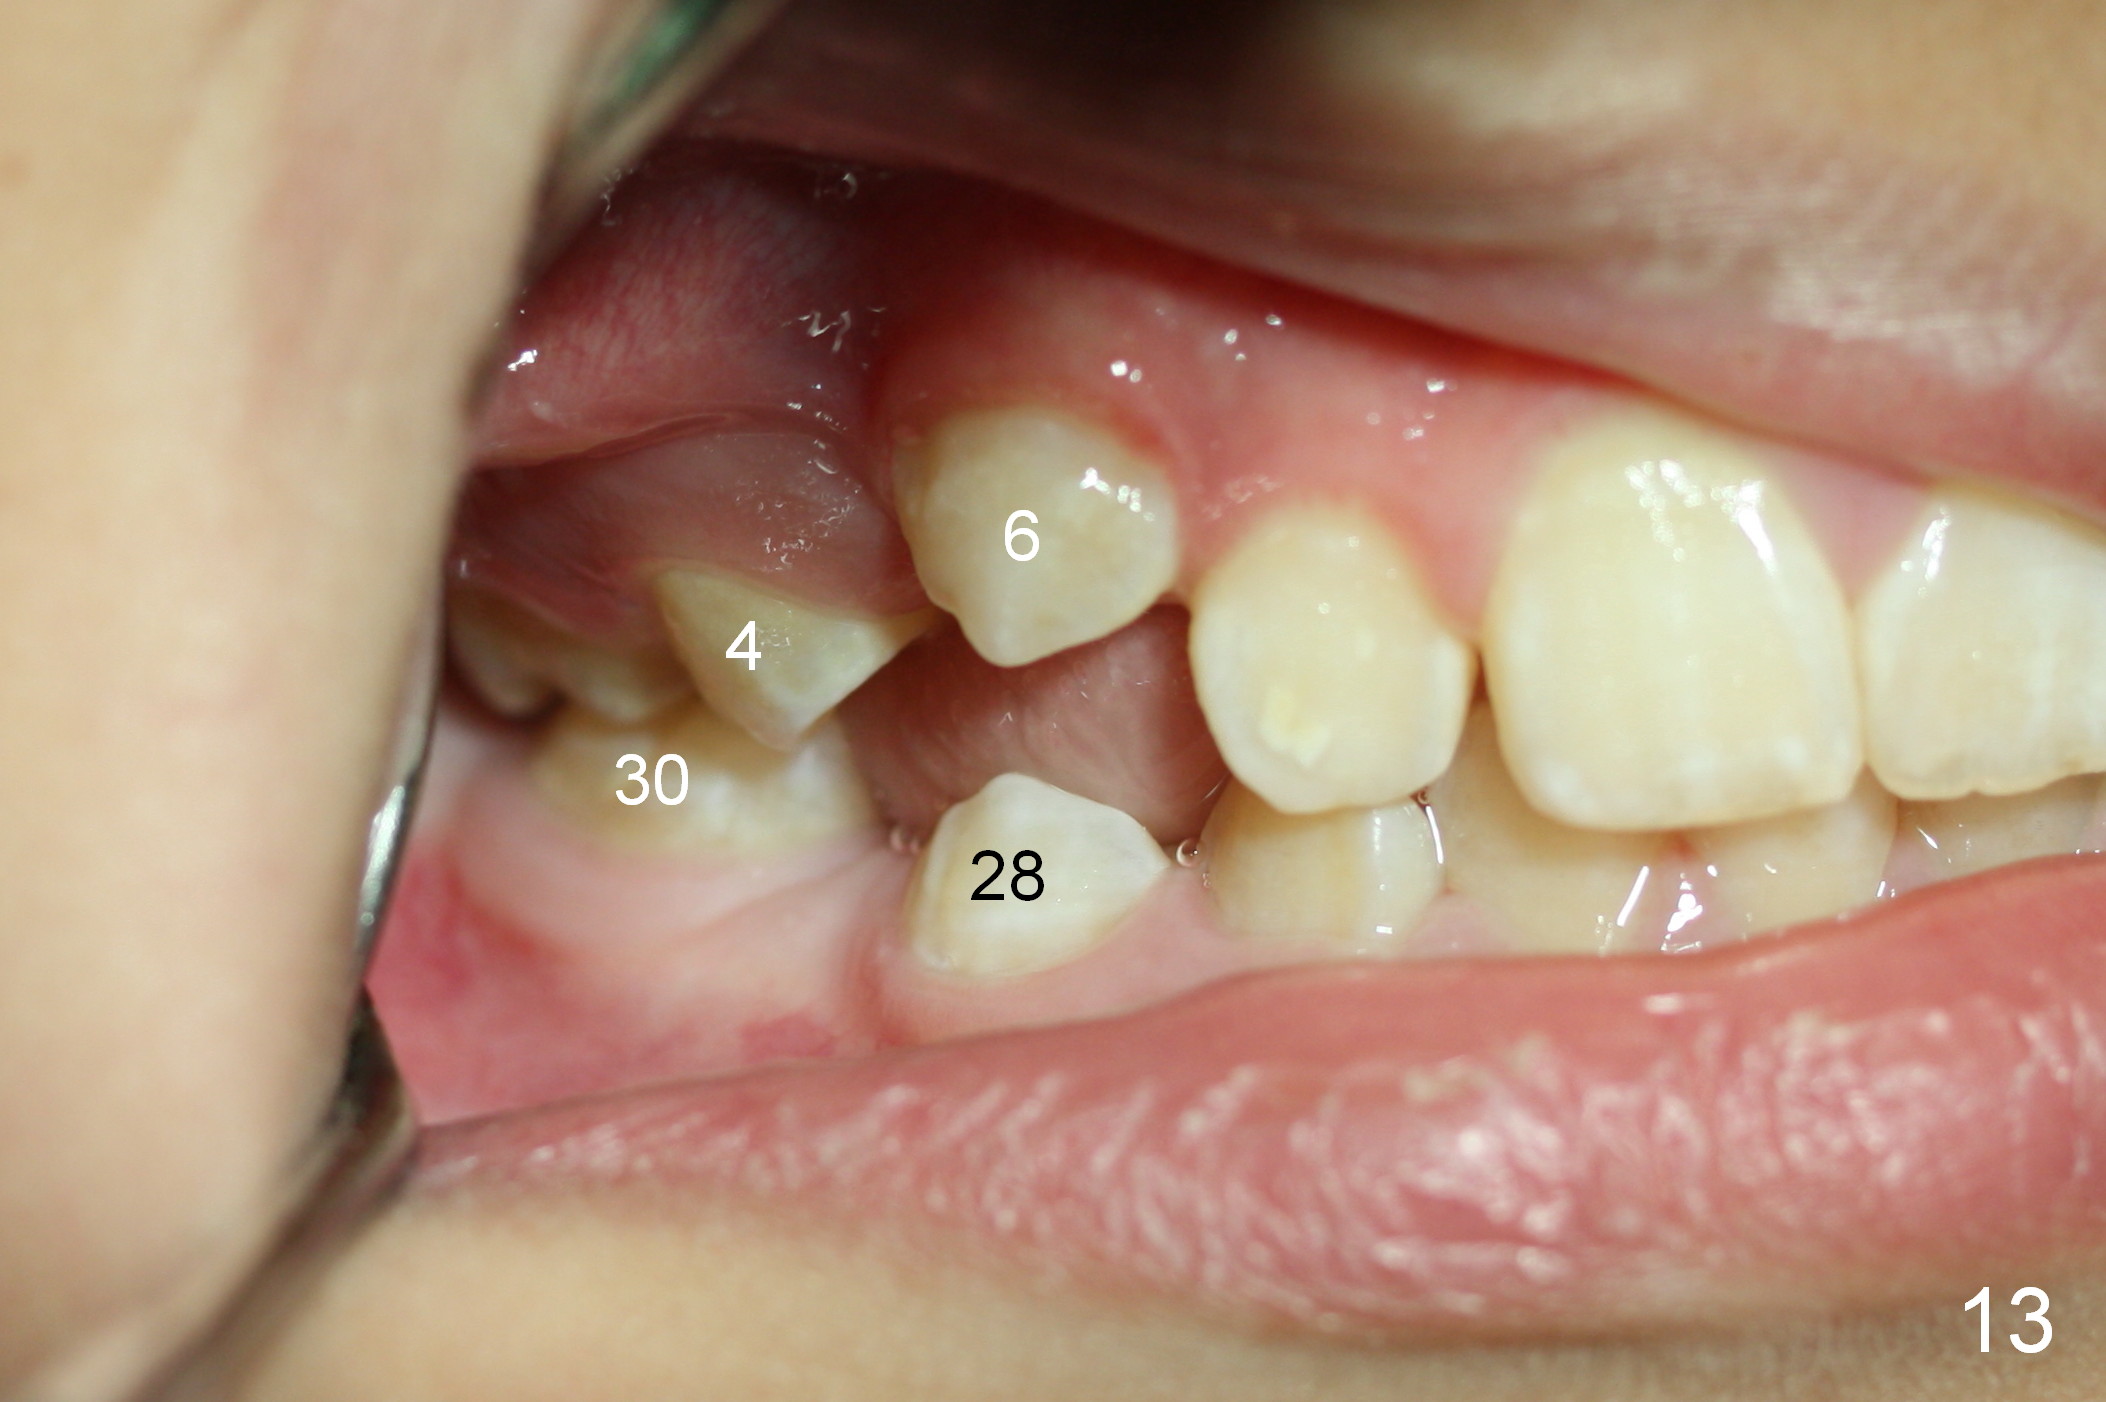

At age of 6 years 1 month, Linwei (boy) has crowding problem, especially in the lower right quadrant (Fig.1). At 9, the crowding also involves the upper right and lower left quadrants (Fig.2). A bilateral space regainer is placed for the lower arch a month later.

Another 1 month, the teeth #4 and 6 are erupting (Fig.11,12). The tooth A is to be extracted. It is assumed that the diastema between #7 and 8 (due to #7 mesial shift in turn due to #6 erupting, Fig.11 arrow (as compared to Fig.6 <)) will be closed once the tooth #6 erupts fully.

Two months later (9 years 8 months old), the teeth #4 and 6 are partially erupted (Fig.13), while the tooth #29 needs surgical extraction. The tooth #20 is erupting; the spacer is going to be removed (Fig.14).